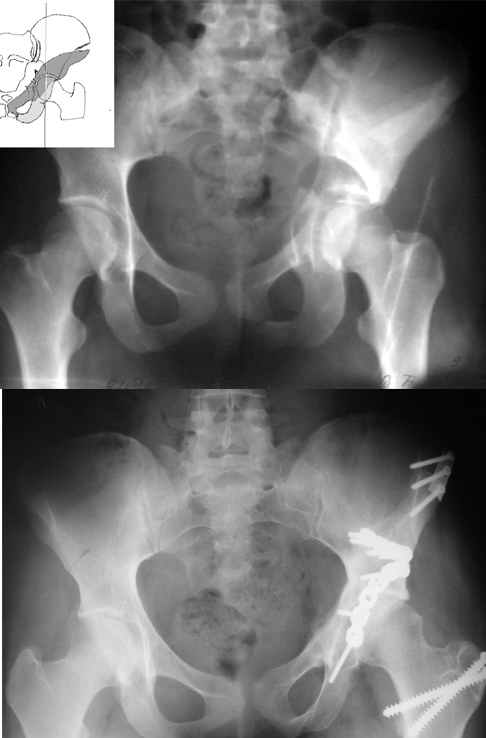

А какой отдел вертлужной впадины более важен передний или задний? Чем был обусловлен выбор доступа к суставу? Проще говоря, почему вы пошли передним доступом на двухколонный перелом? Мне понятны ваши сомнения, когда не удется сделать все что хотелось бы. В данном случае доступ должен быть чрезвертельным боковым (как и советовал Рунков) или двумя доступами.

Вопрос доступа к вертлужной впадине при остеосинтезе задача не простая. Конечно, у Летурнеля и Тайла всё давно описано, нам остается только брать на вооружение. Но сами понимаете, что не бывает двух одинаковых ситуаций, поэтому в каждом случае вопрос решается сугубо индивидуально. Наша главная цель - восстановить анатомию с нанесением минимальной дополнительной травмы тазобедреннному суставу, думаю с этим никто не поспорит. Расширенный илиофеморальный доступ уж слишком травматичен (как сказал один коллега "таз лежит отдельно, больной отдельно").Стоит ли делать из пациента анатомический препарат для того чтобы легче ориентироваться. Да и нужно ли собирать всю "мозаику"? Мы применяли при таких операциях своеобразную операционную хитрость - сначала устраняли грубое смещение крыла под гребнем с фиксацией так называемой "плавающей" пластиной (временно фиксированной на двух винтах)- доступ или продлевали боковой, или делали небольшой дополнительный разрез над гребнем. Это позволяло устранить грубое смещение и захождение отломков тела повздошной кости, что значительно облегчало репозицию и остеосинтез впадины над сводом. Основное внимание конечно же уделяли нагружаемому задне-верхнему отделу. Сообщите ваш адрес, пришлю схемы и рентгенограммы.